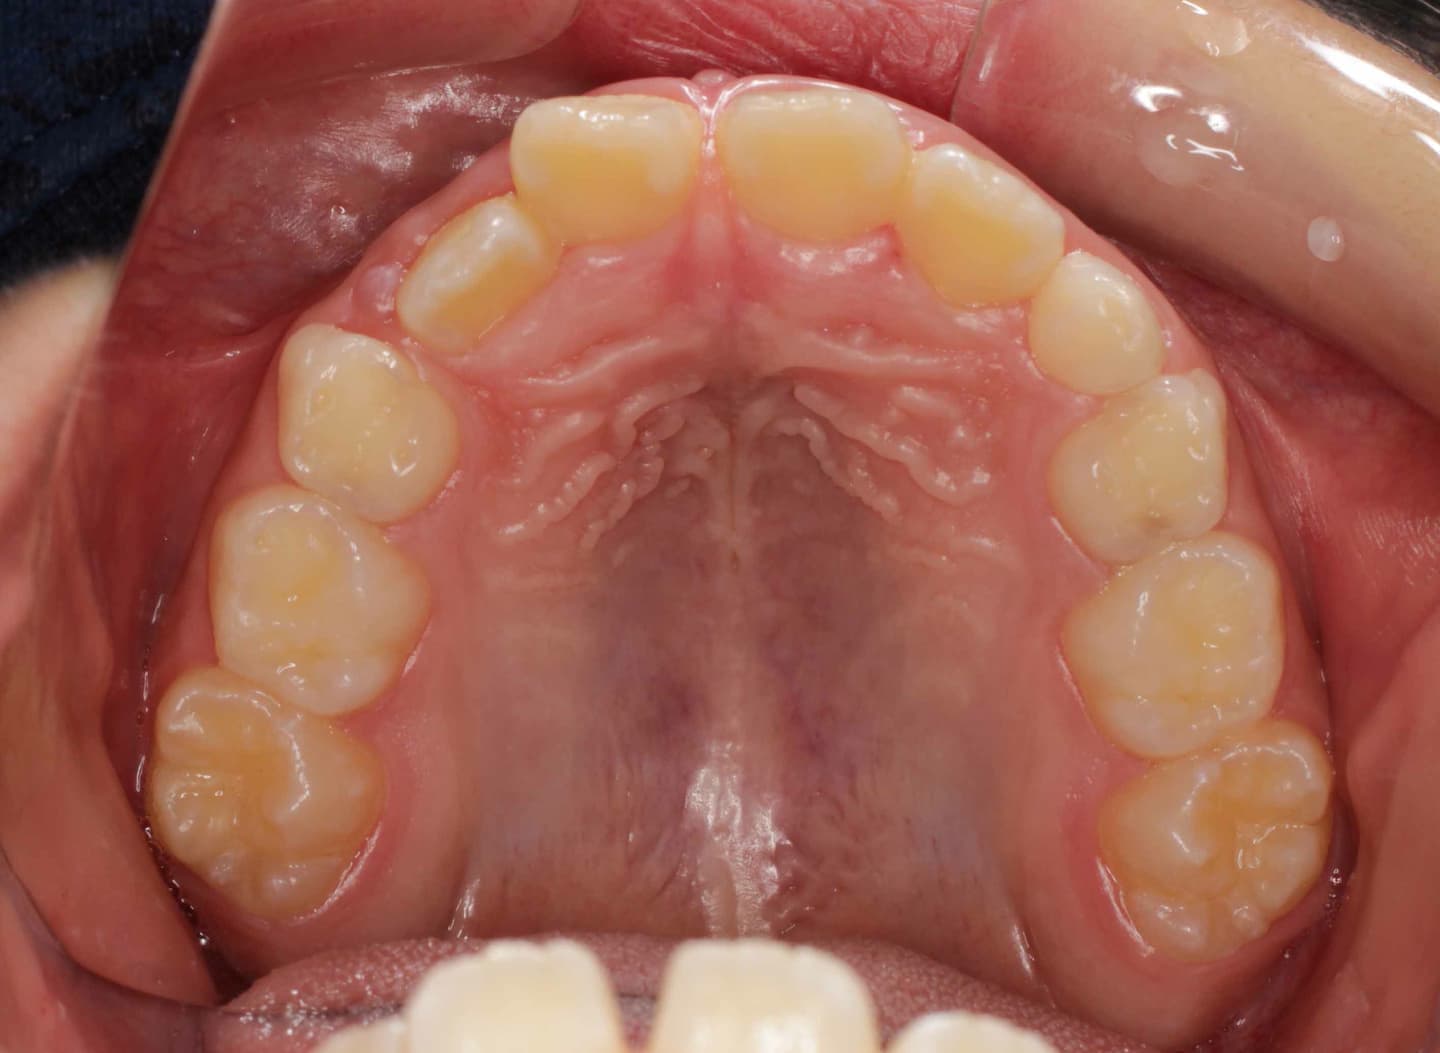

診断:初診時では右上3番の萌えるスペースがほとんどなく、顔と上顎と下顎の正中に対して、上顎前歯の正中が右にずれこんでいます。その影響で右上2番が右下乳歯Cと反対咬合になっています。放置すると、右上3番が埋伏歯になり、下顎の成長が左方向に流れるので、成長とともに顔面の非対称が増悪されることが予測されます。

治療前

右上乳犬歯が既に脱落しており、右上犬歯の萌出スペースがゼロになっています。